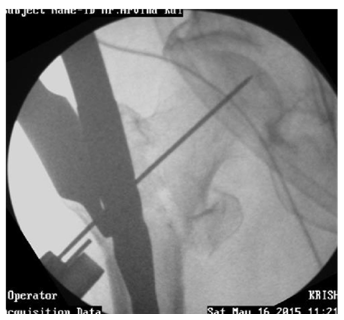

Use of curved femur finder device, retractor push, cannulated curved awl to pass the guide wire in correct direction (Figures 14-17).

Figure 14 Guide wire in canal deviating medially.

Figure 15 Redirection by Retractor push, Femur finder, Cannulated awl.4

Figure 16 Guide wire going medially sometimes can exits out through fracture and damage neurovascular structures.

Figure 17 Redirected Guide wire in canal.